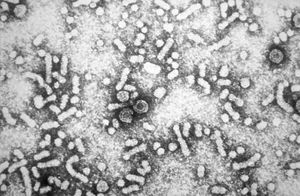

يتبع ڤيروس التهاب الكبد ب فصيلة الڤيروسات الكبدية.[9] جسيمات ڤيروس (الفيريون) تتكون من غلاف خارجي من المادة الدهنية ونيكلوكابسيد ايكوساهيدرال تتألف من البروتين. ويحتوى النيكلوكابسيد على الحمض النووي الڤيروسي وبوليميريز الحامض النووي الذي به نشاط عكس المنتسخة.[10] المغلف الخارجي يحتوي على البروتينات التي تعتبر جزءا لا يتجزأ من المشاركة في ملزمة الڤيروسية، ودخولها حيز، وخلايا حساسة. الڤيروس هو واحد من أصغر الڤيروسات الحيوانية التي يلفها الفيريون يبلغ قطرها من 42 نانومتر، ولكن توجد أشكال متعددة الأشكال، بما في ذلك الأجسام الخيطية والكروية التي تفتقر إلى جوهر. هذه الجسيمات غير معدية، وتتكون من الدهون والبروتينات التي تشكل جزءا من سطح الفيريون، وهو ما يسمى المضادات السطحية (HBsAg)، وتنتج في زيادة خلال دورة حياة الڤيروس.[11]

إن ڤيروس التهاب الكبد HBV) B) هو ڤيروس صغير مضاعف القشرة من فصيلة الڤيروسات الكبدية Hepadnaviridae. للڤيروس مجین DNA genome حلقي صغير ثنائي النطاق -double stranded جزئياً. يحتوي ڤيروس HBV عدة مكونات مستضدية هي والمستضد السطحي لالتهاب الكبد HBsA ) B)، والمستضد اللبي لالتهاب الكبد HBcAg) B)، والمستضد e لالتهاب الكبد HBeAg) B). يعتبر الإنسان المضيف الوحيد المعروف لڤيروس HBV، لكن يمكن لبعض الرئيسيات غير الإنسانية أن تصاب بالإنتان في الشروط المخبرية. إن HBV مرن نسبياً، وقد لوحظ في بعض الحالات بقاء الڤيروس معدياً على السطوح البيئية مدة شهر على الأقل في حرارة الغرفة.

أقدم تسجيل لوباء بسبب ڤيروس التهاب الكبد البائي كان على يد لورمان في عام 1885.[34] فقد تفشي مرض الجدري في بريمن في عام 1883 ووقد تم تطعيم 1،289 موظف بالترسانة بالليمف من غيرهم من الناس. وبعد فترة تتراوح من عدة أسابيع إلى ثمانية أشهر، وُجِد أن 191 من العاملين المطعمين أصبحوا مصابين بمرض اليرقان وتم تشخيصهم بأنهم يعانون من التهاب الكبد المصلي. أما غيرهم من الموظفين الذين تم تحصينهم بدفعات مختلفة من الليمف فقد بقوا بصحة جيدة. ورقة Lurman الآن تعتبر مثالا تقليدياً لدراسة وبائية، أثبتت أن الليمفات الملوثة كانت مصدر المرض. لاحقا، وقعت العديد من التفشيات المماثلة بعد بدء الاستخدام، في عام 1909، لإبر الحقن، والأخطر من استخدامها كان إعادة استخدامها، لحقن سالڤارسان Salvarsan لعلاج مرض الزهري. ولم يُكتشف الڤيروس حتى عام 1965 عندما كان باروخ بلومبرگ يعمل في المعاهد الوطنية للصحة، اكتشف مضاد أستراليا (المعروف لاحقا بمضاد الالتهاب الكبدى ب السطحي، أو HBsAg) في دم السكان الأصليين الأستراليين.[35] على الرغم من أن الڤيروس أصبح مشتبه به منذ نشر البحث في ماكالوم في عام 1947 [36]، اكتشفت د. س. دين وغيره جسيمات الڤيروس في عام 1970 بواسطة المجهر الإلكتروني. [37] في بداية 1980، جينوم الڤيروس قد تم على مراحل متتابعة [38]، وكانت أول اللقاحات التي يجري اختبارها.[39]